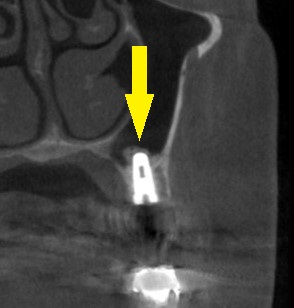

下の写真2段目が術前のCT、やや骨が薄いのが分かります。

下の写真3段目が術後のCT、ソケットリフトによりインプラントが埋入され周囲に骨補填材が白く写っています。